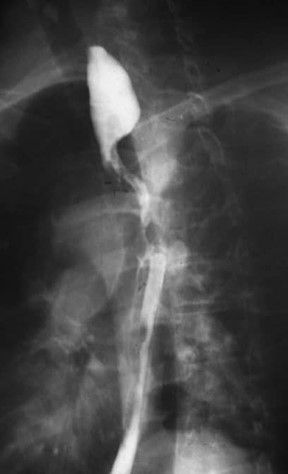

Uống bari: Đây đôi khi là xét nghiệm đầu tiên được thực hiện ở những người bị khó nuốt. Đó là một loạt các phim X-quang được chụp sau khi bạn nuốt bari, một chất lỏng sánh màu trắng có khả năng hiện diện trên phim X-quang. Bất kỳ khối u nào trên lớp lót bên trong của thực quản đều xuất hiện trên phim X-quang.

Uống bari: cho thấy sự tắc nghẽn do ung thư. Nguồn Medscape.com